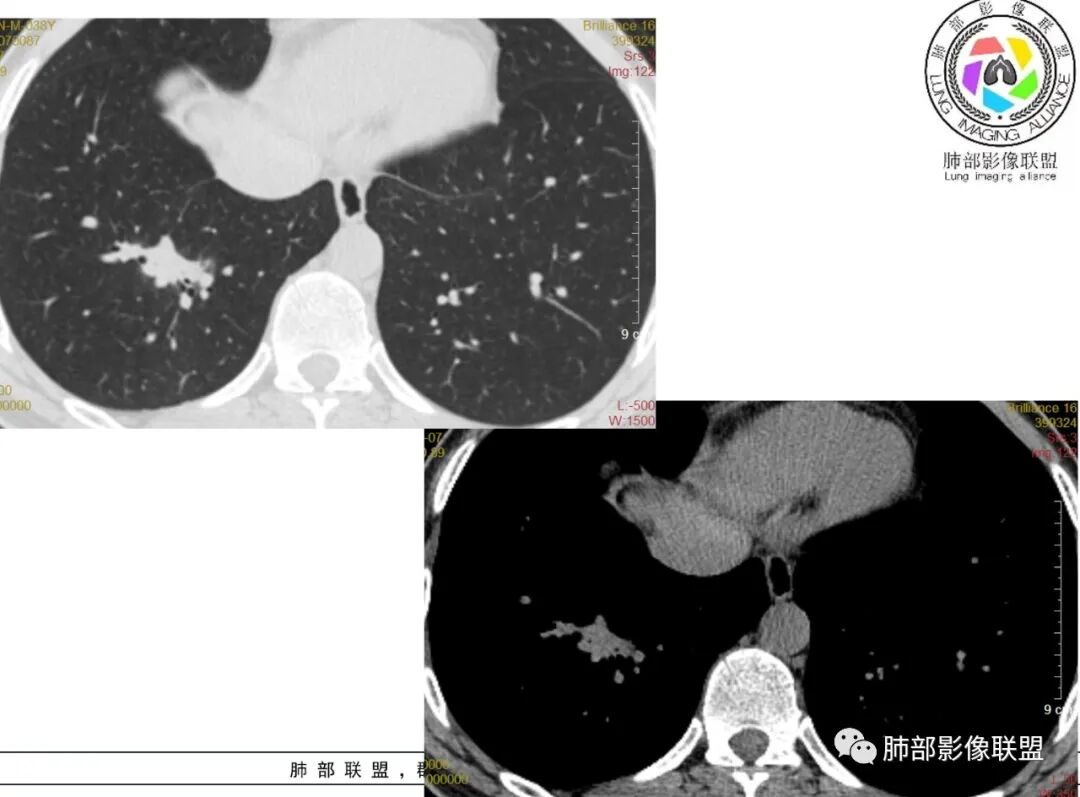

尘缘:中年男性,咳嗽咳痰伴乏力多汗,无发热,偶有畏寒。期间至某中医院治疗服中药后,症状好转。白细胞与血沉稍高。影像表现:左上肺团块状影(增强后CT值约22,伴有血管漂浮),中间支气管明显扩张,伴有小空洞形成,周围有晕,右下肺多发团块状影(增强后CT值约48),无明显支扩,伴胸膜下多发小结节,13天后复查,左上肺主病灶无明显变化,其他病灶范围有缩小,空洞消失,右下肺病灶变化不明显。

可能诊断:1、二元:左上肺淋巴瘤,强化程度较轻,明显支扩,血管漂浮,治疗后左上肺病灶有好转(考虑为周围渗出减轻,空洞消失所致),右下肺感染性病变,有感染的临床症状及白细胞增高,伴周围多发结节(卫星灶),治疗后无明显变化。病原体:隐球可能性大,鉴别结核,非典。2、一元:整体都考虑感染,那就形成了多形,多态,结核要考虑在前面,临床有咳嗽,咳痰,伴乏力,多汗,支持,影像也可以。一元隐球,左肺病灶形态不支持,支扩太明显,强化程度两肺相差大,所以可能较小。一元类鼻疽,没有糖尿病史,没有下田劳作史,可能小,再加上临床症状无发热,影像无明显SPE改变,无其他系统多发脓肿,而且中药治疗还有一定效果,不太符合。

2、影像资料:双肺多发的小结节、斑片状及不规则型的实性病灶,周围有晕,沿支气管血管束分布,部分的病灶周围可见磨玻璃样影、支气管的扩张以及小的空洞。增强扫描病灶,轻度强化内部见支气管造影征。部分的病灶,支气管有扩张,内壁凹凸不平的改变,纵隔淋巴结未见肿大。病灶整体的形态还是多样化,部分位于胸膜下。

病例资料:男性,48 岁。因“反复咳嗽、咳痰1 周,加重伴气促2天”于2018 年9 月7 日入院。外院胸部CT示右肺炎,经治疗后无好转,来我院急查血常规示:白细胞9.2× 10^9 /L,N% 84.9%。超敏CRP:462.52mg/L。降钙素原>100ng/ml。葡萄糖19.6mmol/L。血酮体(+)。查体: 体温:40.2℃,呼吸:32次/分,脉搏:164次/分,血压:100/

38mmHg( 多巴胺维持) 。呼吸机辅助呼吸,双下肺可闻及较多湿啰音,心率齐,未闻及杂音。诊断:重症肺炎呼吸衰竭、感染性休克、2型糖尿病并酮症酸中毒。

本病例肺部病灶累及双肺,以右中上肺的浸润状团块影为主要表现,伴有双肺结节影及胸腔积液,后期局部空洞形成。类鼻疽肺部病灶吸收缓慢,发病第22天时肺部病灶仍无明显变化,发病第65天时肺部病灶仍未完全吸收。本例患者出院后1个半月仍抗感染治疗,经随访无复发表现。